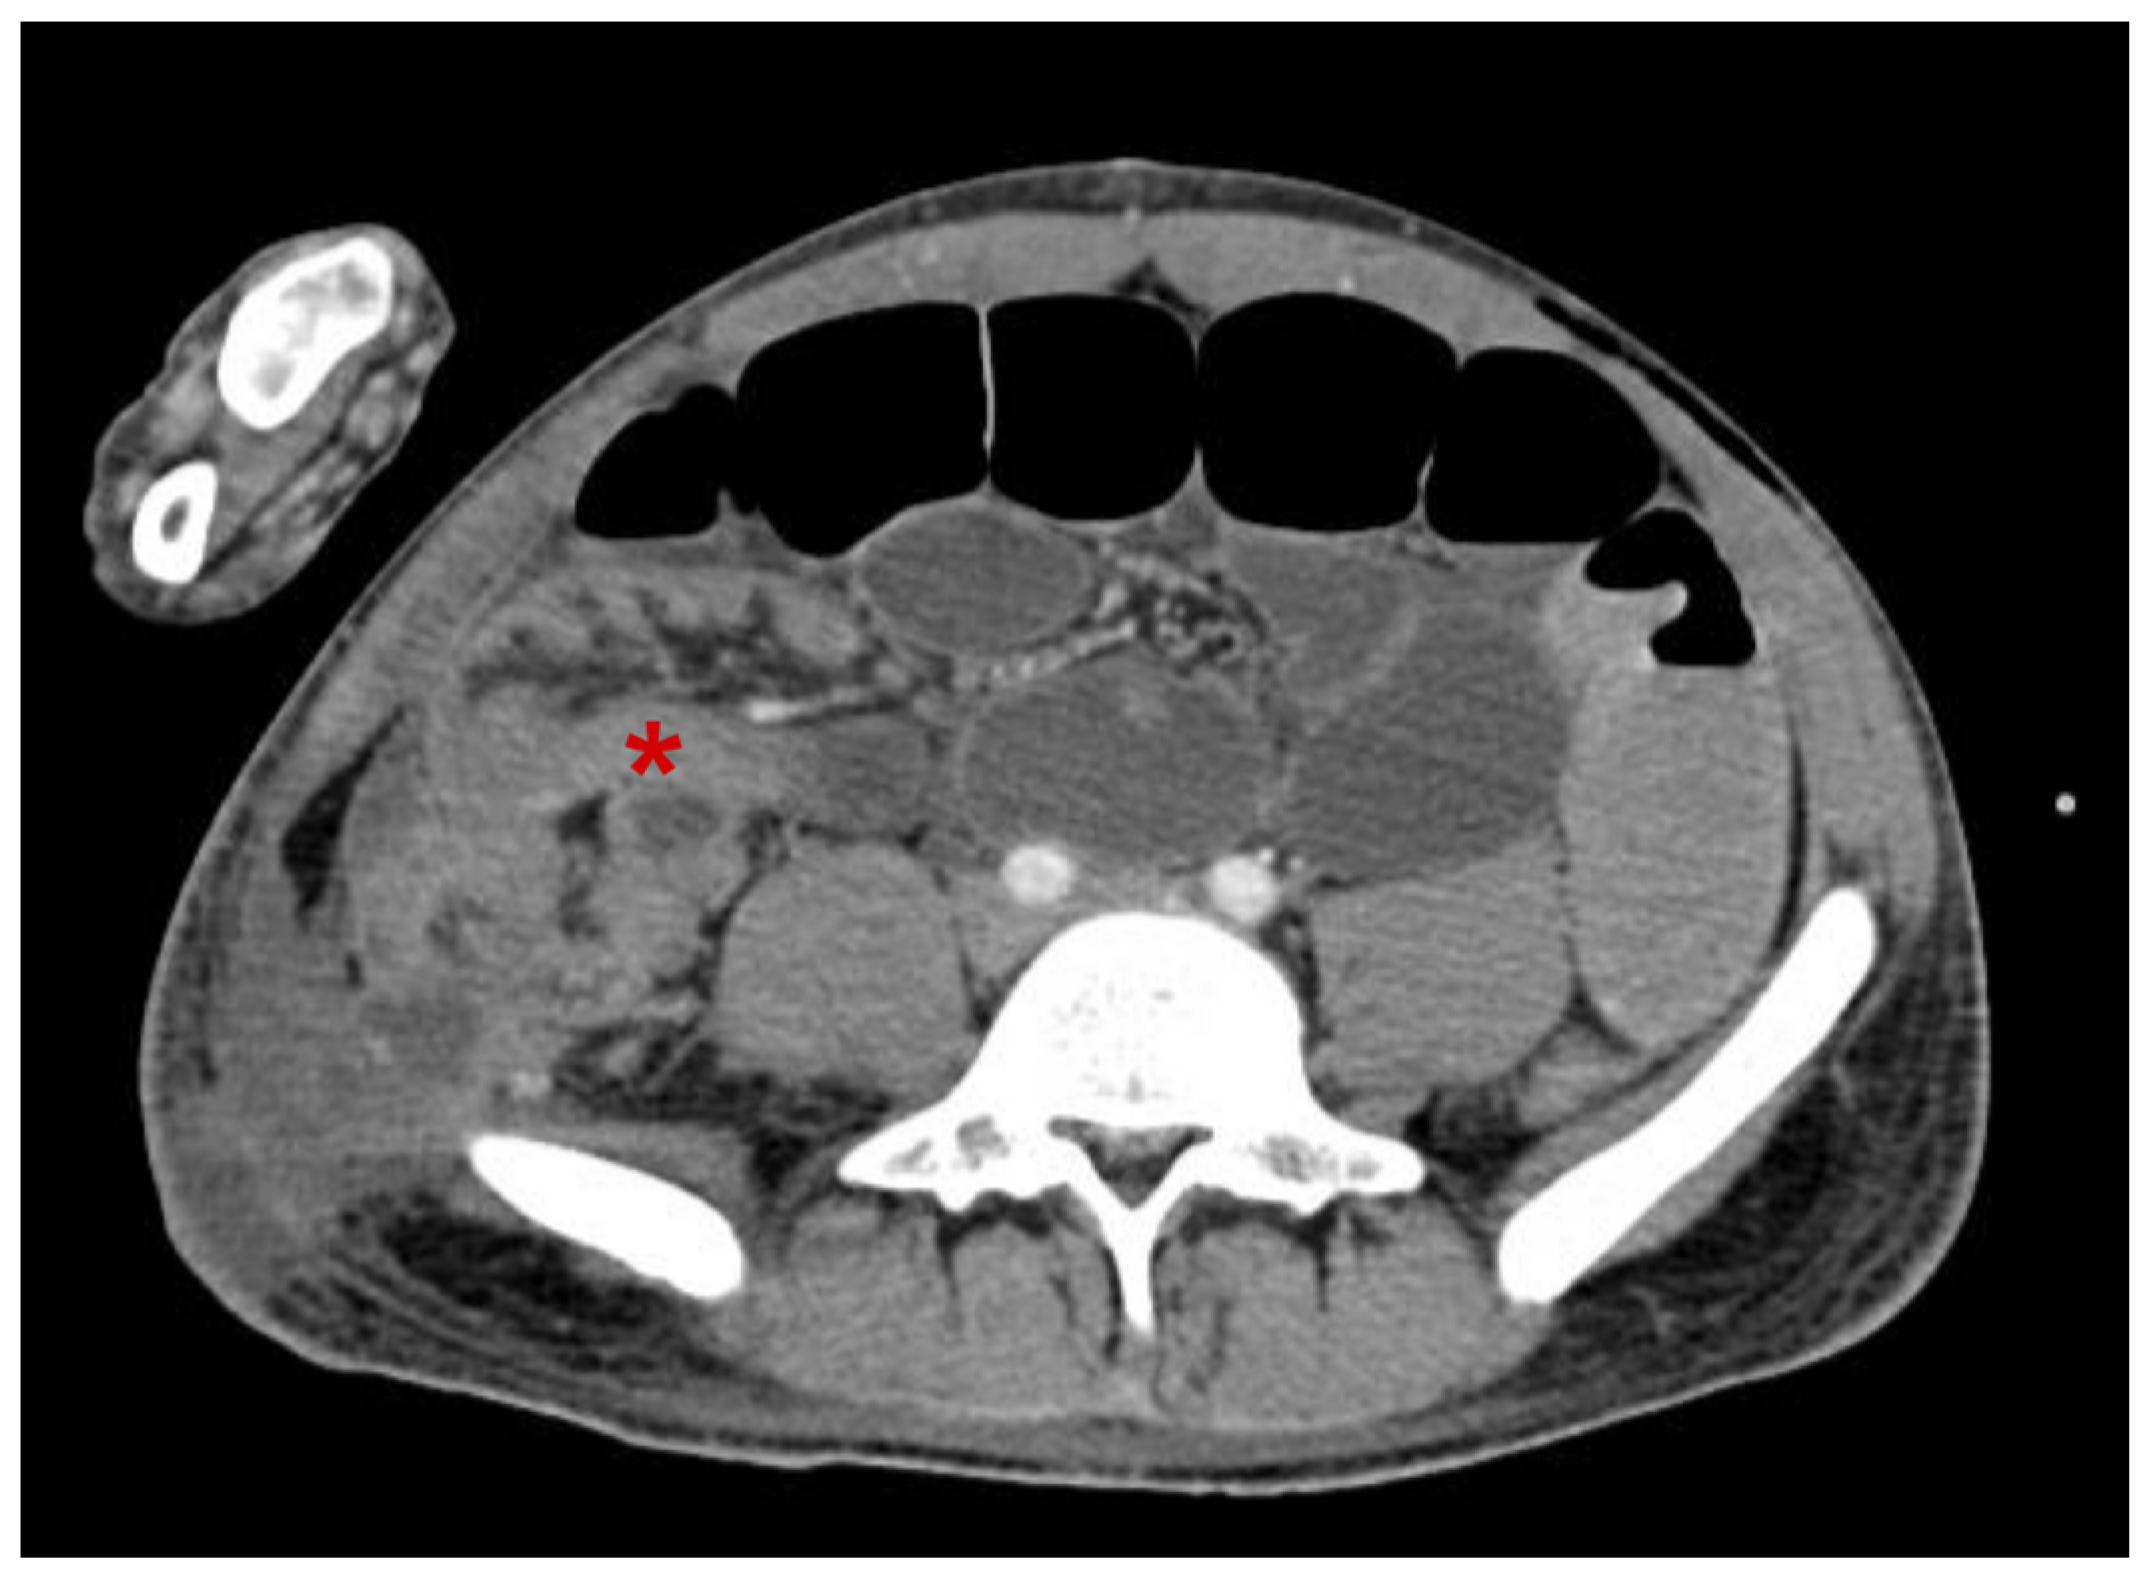

2. Case Report